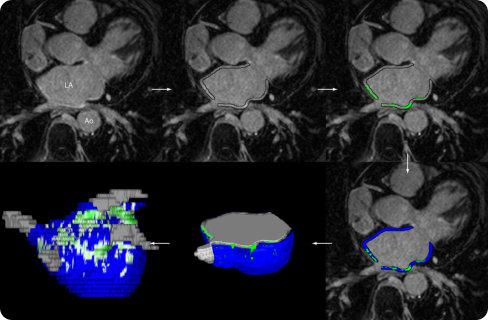

Merisight Image Analysis can help physicians address this shortcoming by providing unique insights into patients’ underlying atrial enhancement, using LGE-MRI pulse sequences and optimized MRI acquisition settings developed by MRI physicists from the University of Utah CARMA Center.

Tools used in the Merisight service incorporate groundbreaking algorithms for 3D image processing and volume visualization to produce detailed models of patient heart structures. It quantifies the extent of the enhancement in the left atrium and computes the amount of AF progression into one of four stages, as defined by the Utah Classification, based on DECAAF research.